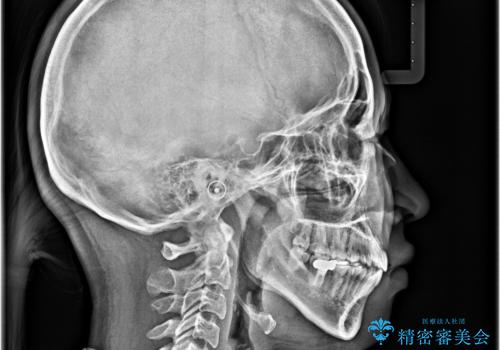

舌突出癖の改善トレーニングは、仕上がり、治療期間、そして治療後の後戻りに大きな影響を及ぼします。

トレーニングをしっかりと行っていただいたため、スッキリとした口元に仕上がりました。